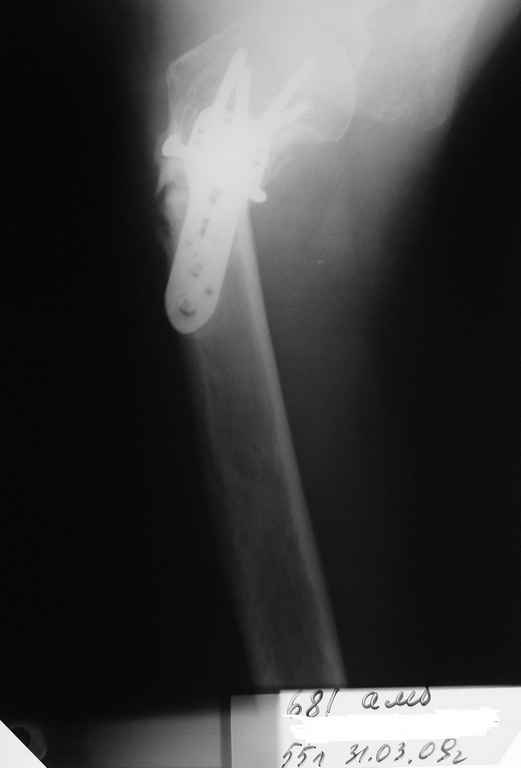

Пациентка Б.1953 г.р., врач-терапевт. Травма 27.11.08г. Падение с высоты роста. Выявлен закрытый не осложненный оскольчатый перелом хирургической шейки левого плеча со смещением. 02.12.08г. оперирована. Выполнена открытая репозиция и остеосинтез пластиной LCP Деост с дополнительной фиксацией отдельно лежащего фрагмента винтом. Послеоперационный период протекал без особенностей, заживление раны первичным натяжением. Швы сняты через 10 дней. Иммобилизация левой верхней конечности клиновидной подушкой 4 недели. По окончании срока – рентген-контроль и умеренная разработка плечевого сустава. В течении месяца функция левого плечевого сустава восстановилась удовлетворительно: поднятие руки до 110 гр., отведение - 90 гр. и до 110 гр. отведение с лопаткой. Отведение руки назад – 20 гр. Наружная и внутренняя ротация – 20 гр. Пациентка по настоянию самостоятельно вышла на работу. 27.03.09 при контрольном осмотре жалоб не предъявляет, болевой синдром в левом плечевом суставе отсутствует. Отведение плеча активно до 90 гр, пассивно с лопаткой до 110 гр., поднятие – 110 гр, отведение назад 20 гр, наружная и внутренняя ротация по 20 гр. На контрольных рентгенограммах отмечается смещение металлоконструкции, ротация головки плеча с приведением дистального отломка на 13 гр. и смещением к зади на 30 гр. Рентгенограммы прилагаются. Ваш взгляд на дальнейшую тактику лечения пациентки?

Рентгенограммы действительно с дефектом укладки, но интраоперационная репозиция, можете поверить, была удовлетворительная как в акcиальной, так и в сагиттальной плоскостях. Интраоперационная рентгенограмма прилагается, хотя укладка тоже на ахти. По тактике - разделяю Ваше мнение об отсутствии необходимости реостеосинтеза, а тем более об эндопротезировании, хотя это все было предложено пациентке ведущими ортопедами-травматологами России.

Здесь пример открытой репозиции 57 летнего с переломом плеча (1,2) смещение обнаружено на интероперационном снимке. При нормальной прямой проекция (3) угловое смещение обнаружили в аксиальной проекции (4)

После устранения смещения пластина установлена выше (5,6,7) и финальные снимки (8,9,10)